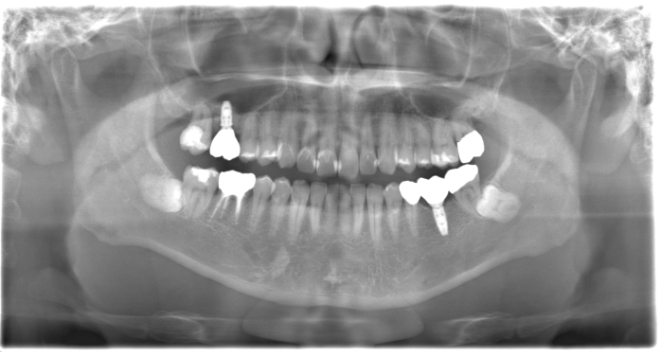

インプラント、ソケットリフト、ダイレクトボンディング、ジルジニアクラウン

| 治療期間 | 1年6ヶ月 |

| 治療費 | インプラント1本500,000円 ソケットリフト110,000円 ダイレクトボンディング〜ジルジニアクラウン1本30,000円〜170,000円 |

| 年齢・性別 | 40代男性 |

| 備考 | 右上の欠損部へのインプラントを希望で来院されました。 左下のブリッジの下にものが挟まりやすいとのことでブリッジ部分もインプラント埋入を希望されました。口腔内の銀歯も全て綺麗にやりかえたいとのことで、ダイレクトボンディングやセラミックインレーやジルコニアクラウンでやりかえていきました。 右上6番のインプラント埋入時にはソケットリフトで骨造成を行なっています。 見た目だけではなく噛みやすくなりとても満足されています。現在はエアフローのクリーニングやホワイトニングで通院されています。 |